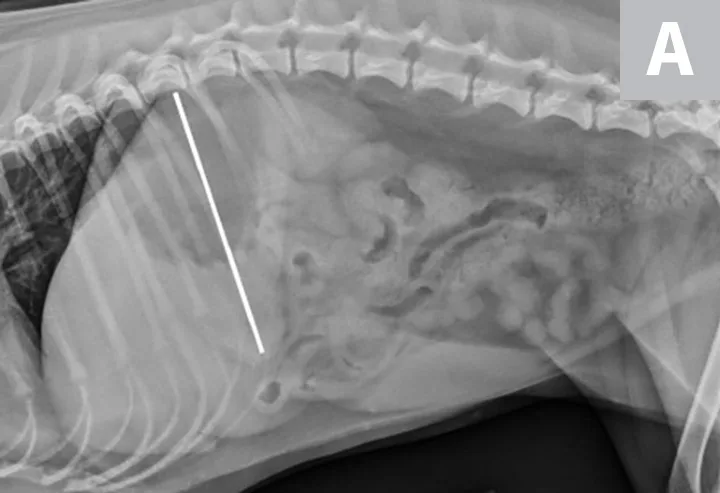

Right lateral radiographs of a clinically normal dog (A) and an 11-year-old neutered male dachshund with diabetes mellitus (B). The dog with diabetes mellitus has a pendulous abdomen and an enlarged liver (ie, hepatomegaly) with rounded margins that extend caudal to the costal arch (B; arrows). The gastric axis (solid lines; aligned with the gastric fundus dorsally to the antrum ventrally) is parallel to the ribs in the clinically normal dog but caudally displaced in the dog with hepatomegaly. Common differential diagnoses for generalized hepatomegaly are vacuolar hepatopathy due to endocrinopathies or other metabolic disease (eg, lipidosis), infectious and noninfectious inflammatory disease, neoplasia, storage disease, and venous congestion.